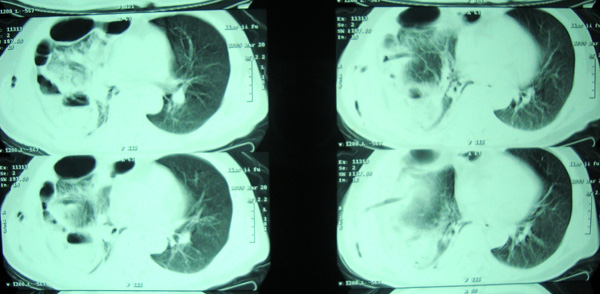

经治疗至17日胸闷痛摄片如9号图,20日复查如7,8号片.

结论:右侧大量胸腔积液,可疑膈下脓肿.

20日院外ct检查,片示于后.

1)考虑右肺感染性病变(化脓性肺炎或肺脓肿可能)。2)右侧液(脓)气胸,部分包裹。

考虑1、右膈下脓肿并肺脓肿,2、右侧液气胸

右肝上间隙积液,支持考虑膈下脓肿,

右侧脓胸、右膈下脓肿。不除外右肺化脓性肺炎。

右侧膈肌抬高明显,胸腔内无明显积液,表现为胸膜反应,肝脏周围大量积液,并见多个液气平面。右下肺不均匀密度增高影。结合临床考虑右侧膈下脓肿并腹腔内积液、右下肺并发感染及胸膜反应,节段性肺不张不除外。

右侧肺脓肿,右侧包裹性脓气胸

右肺下叶见大片状病灶,密度不均,其内见透光区。沿右侧胸壁见多发含气腔,其间可见间隔,其内部分可见液平。膈肌下未见异常(纵隔窗窗位太低)。应该是典型的化脓性肺炎合并脓胸。

右隔下积脓并右侧肺脓肿;右侧液气胸